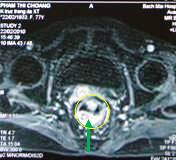

Sau điều trị hóa-xạ trị 23 ngày: khối u trực tràng đã thu nhỏ kích thước hơn trước